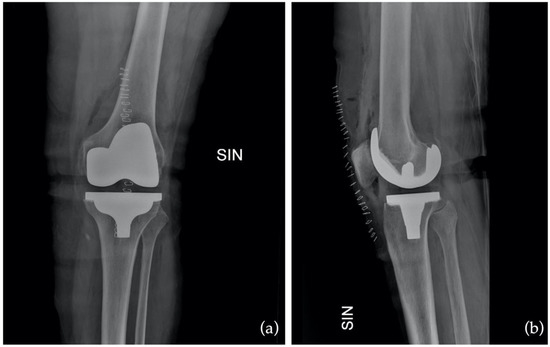

Figure 7.

Postoperative X-ray in anteroposterior (AP) as (a) and in latero-lateral (LL) as (b).